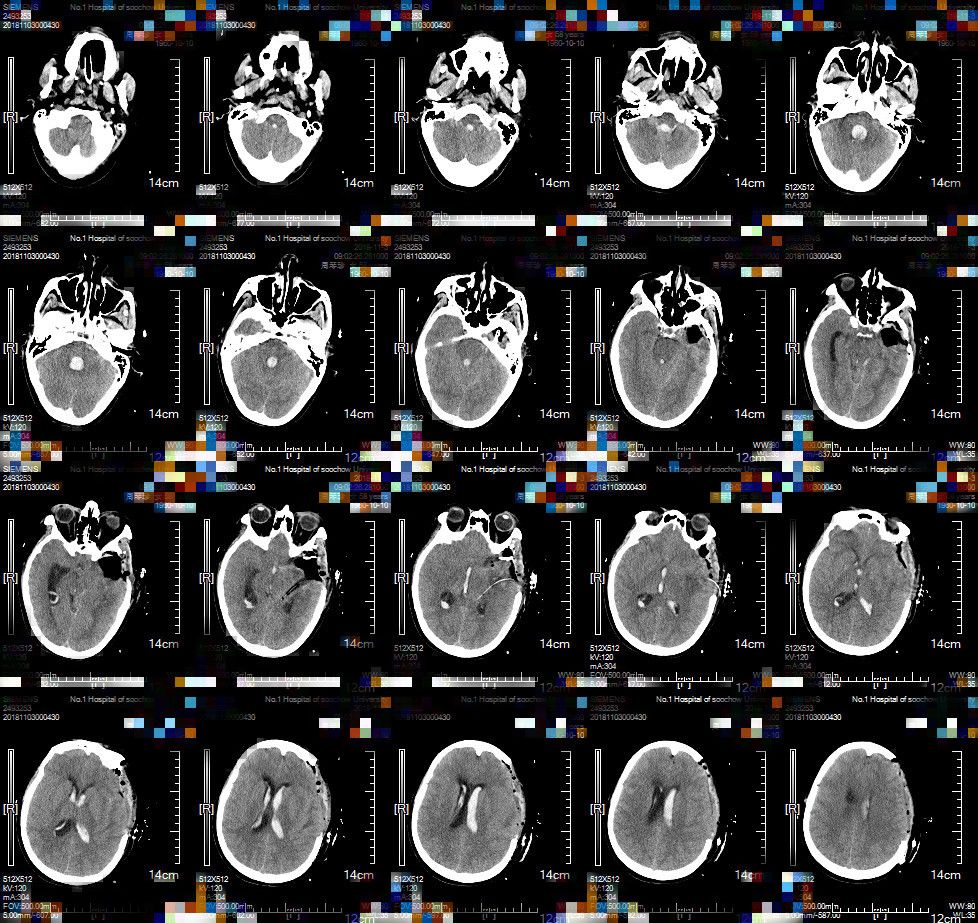

急诊查头部CT提示左侧颞叶脑出血,侧脑室、三脑室、四脑室/环池血肿,伴有蛛网膜下腔出血,较前(外院头部CT)未见明显进展(图1)。CTA示:左侧颞部动静脉瘘伴瘤样扩张(图2)。

图1. 头部CT示左侧颞叶可见一边界清楚、形状不规则高密度影,其内可见部分低密度影,左侧侧脑室受压明显,左侧侧脑室、三脑室、四脑室、环池可见高密度影,考虑左侧额颞叶出血通过左侧侧脑室后角破入脑室系统。中线结构略向右移位。